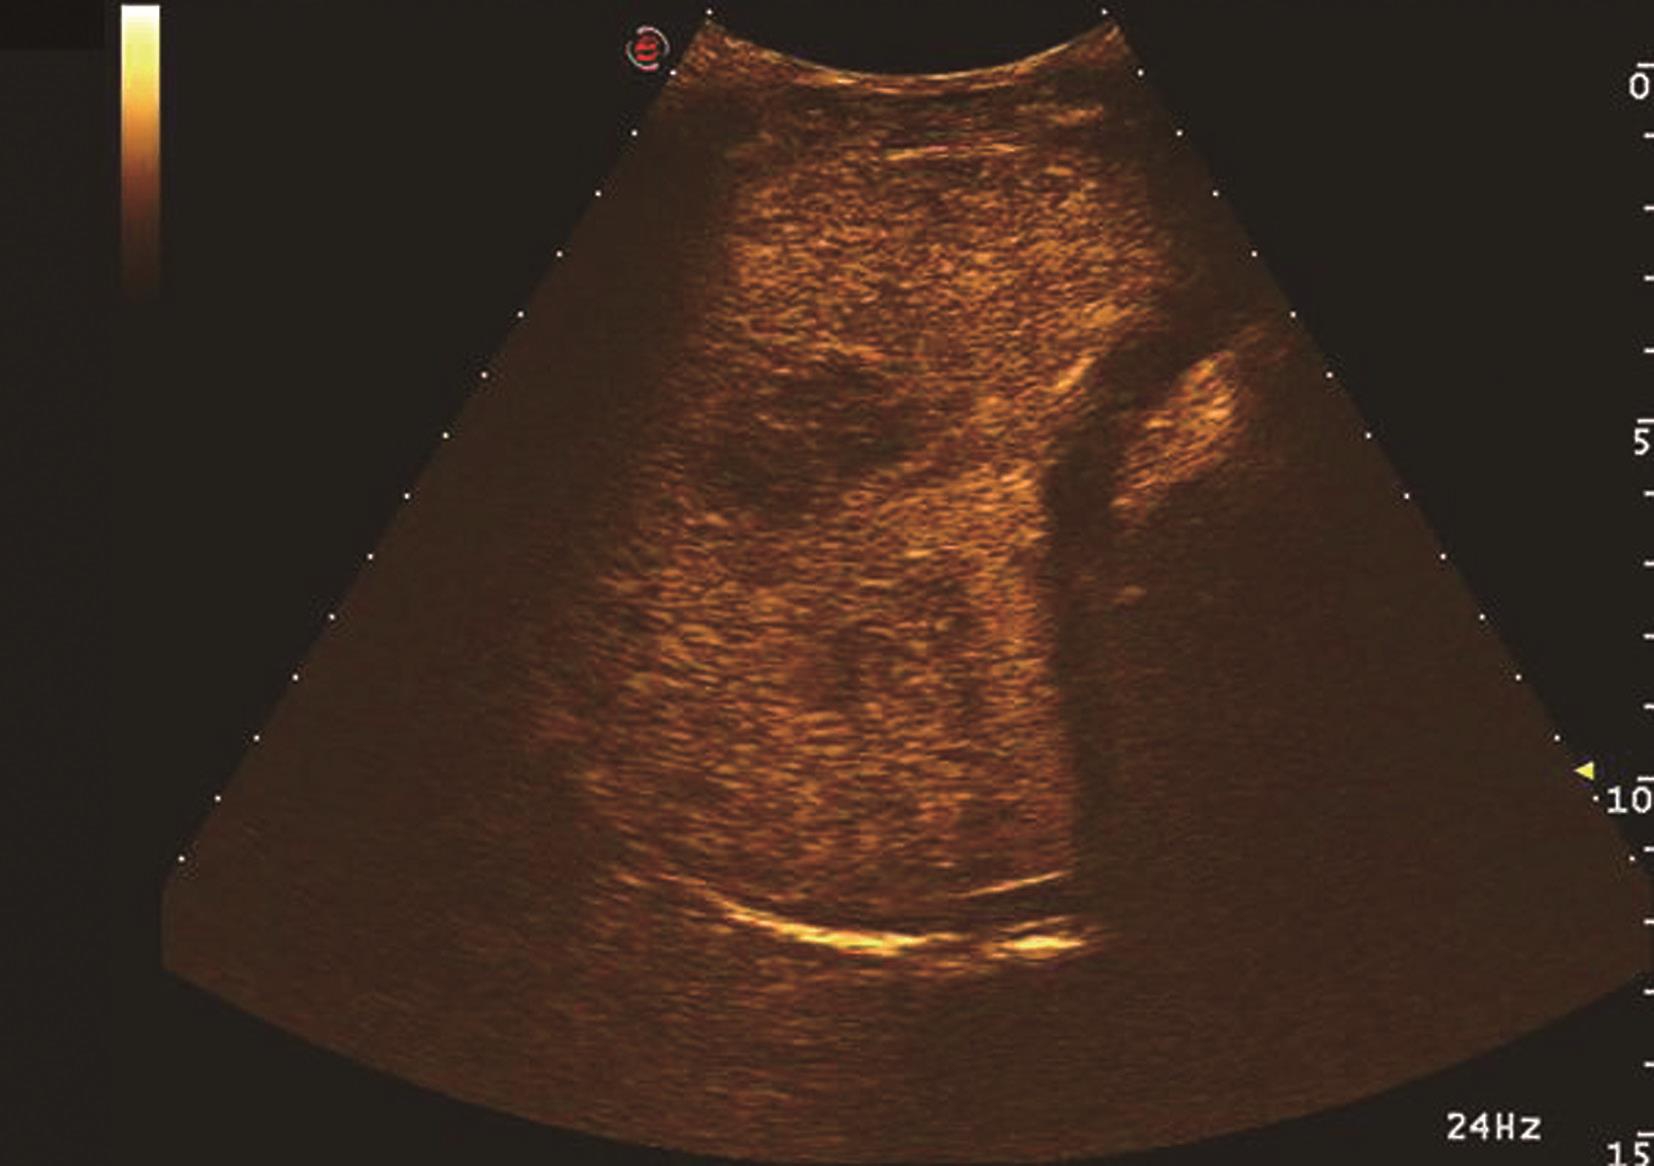

(6)超声造影评估肝硬化:

在肝硬化中,由于肝组织结构的变化,纤维结缔组织的增生,窦周间隙的胶原化,累及肝窦的毛细血管样通道,导致血管空间的减少,通常伴有血流动力学紊乱,肝内多发动静脉分流,其肝静脉显影时间早于正常人群及非肝硬化人群。Albrecht等提出了一种利用声学造影诊断肝硬化的方法,即测量静脉内注射造影剂到肝静脉内出现造影剂信号的时间。肝硬化患者组的超声造影时间-强度曲线显示造影剂度越时间(transit time,TT)明显异于正常组和非硬化性弥漫性肝病组,肝硬化组平均通过TT为18s,继而出现一个早而陡的多普勒强度上升,正常组和非硬化组TT分别为52s、39s,而后出现一个较迟而缓慢的多普勒信号上升,推测造成肝硬化通过时间缩短的原因可能是肝内动静脉短路。在有明显的肝动脉和门静脉短路时,动脉相和门静脉相几乎同时出现。Abbattiasta等研究表明肝静脉显影时间17s为诊断肝硬化的阈值,且显影时间与肝弹性检查密切相关,弹性值越大,肝静脉显影时间越早。